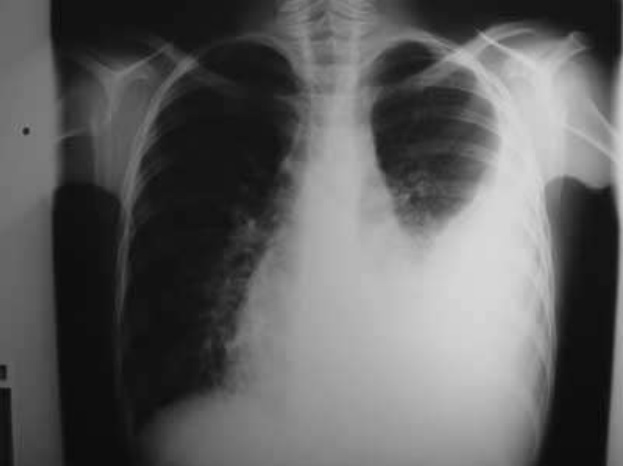

- La acumulación de líquido en la cavidad pleural puede ser pequeña (500-1000 ml), mediana más de 1500 ml; o grande más de 3000 ml; puede ser libre o enquistado; y finalmente, puede ser un trasudado (hidrotórax), un exudado serofibrinoso (pleuresía), un exudado purulento (empiema) o sangre pura (hemotórax). La sinología va a depender en gran parte de estas variables pero, tomando como ejemplo un derrame pleural libre y de más que mediano volumen, tendremos:

La curva de Ellis-Damoiseau es una línea de concavidad superior que se obtiene por percusión o Rx, e indica el límite de un derrame pleural.